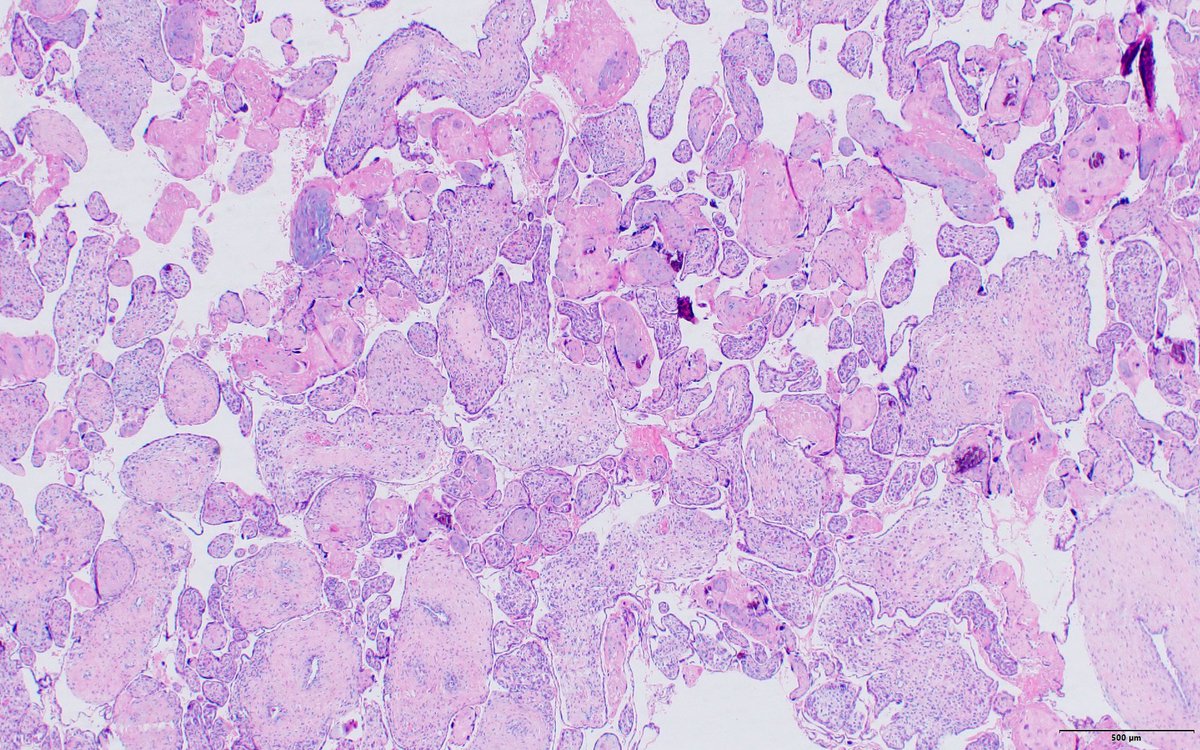

Given the placenta findings what are we worried about for the newborn? 👶 #PathTwitter #PathX #PediPath #PlacentaPath